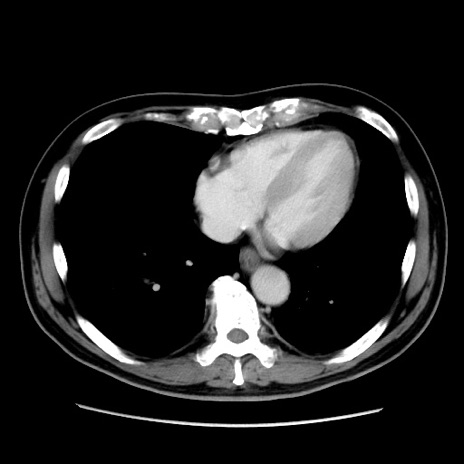

冠状断像

【症例】 70歳代男性

【主訴】 腹痛、嘔吐

【現病歴】 約1ヶ月前より間欠的に腹痛と嘔吐あり、当院消化器内科を受診したところCTで多発する肝臓のLDAを指摘され、精査中であった。以降は消化器症状は安定していたが、2日前より嘔気と腹痛があり、同日より排便・排ガスが消失した。改善認めず、 本日、救急外来を受診した。

【既往歴】 大腸ポリープ切除後。

【身体所見】意識清明・会話良好、BT 36.3℃、BP 127/80mmHg、 P 80bpm、腹部:膨満あり、平坦・軟、上腹部正中および下腹部正中に圧痛あり、反跳痛なし、筋性防御なし。

【データ】WBC 7200、CRP 0.77